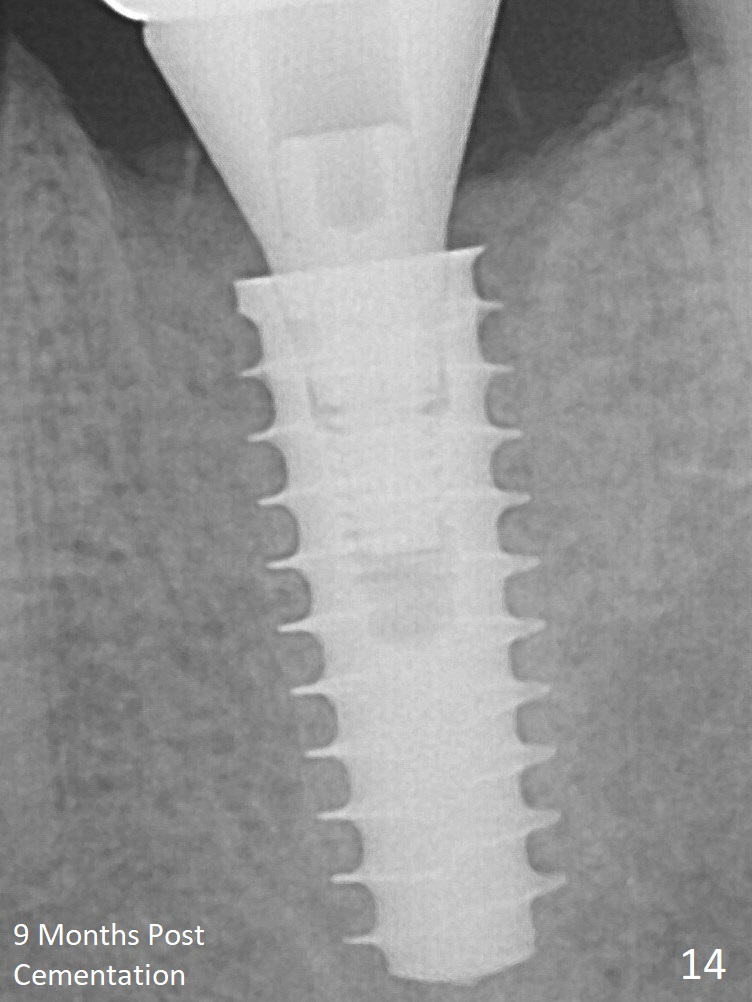

New bone has apparently covered the implant plateau 8 months postop (3 months post cementation (Fig.13 arrows)). The lower two-thirds of socket have disappeared. Bone density between threads increases 9 months post cementation (Fig.14). There is 2 mm bone superior to the implant plateau mesial and distal 1 year 9 months post cementation (Fig.15,16).